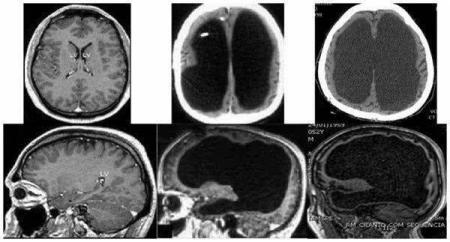

一名44岁的公务员,在税务局上班,一天他觉得左腿有些不舒服,去医院看病,他做了脑部扫描,查看片子后惊讶地发现,这名男子的大脑少得可怜,大部分颅腔充满了脑脊液,只有少量脑组织排列在颅腔内。

更为意外的是,尽管大部分脑组织缺少,他看起来依然很健康,没有精神残疾,还是一名公务员,尽管智商低于正常水平,但是并未影响他在当地税务局执行任务的能力。

另一个“无脑”案例:一个头部异常大的患者。

尽管如此,他的生活并未受到影响。经过检查后发现,他也是一个脑组织缺少患者,只有一层约1毫米厚的脑组织,里面充满了脑脊液,但脑干是正常的。

因此,除了头大,他的呼吸、吞咽、消化、眼球运动和心跳功能都是正常的,不仅如此,他的智商高达126,并获得了数学一级荣誉学位。